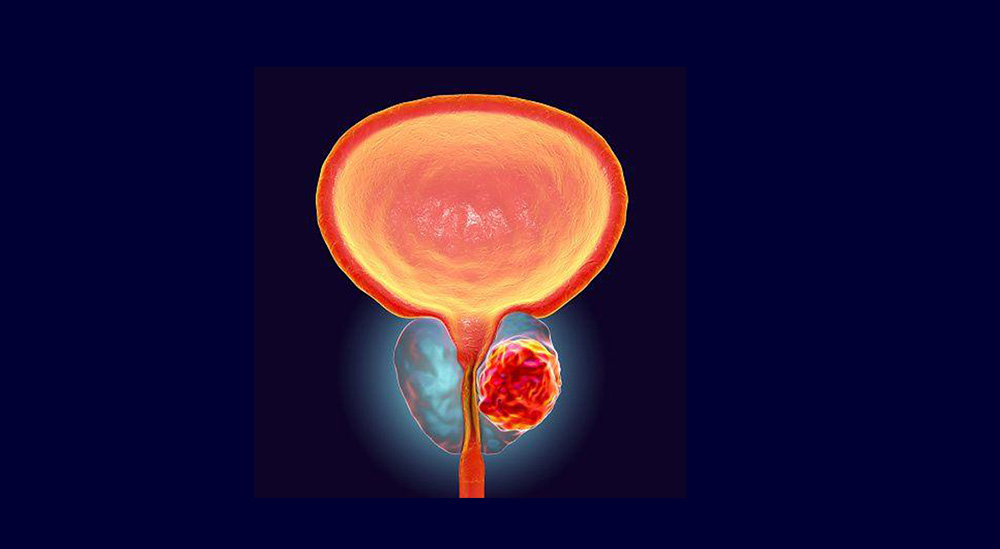

किन बढ्दैछ विश्वभर प्रोस्टेट क्यान्सर ?

प्रोस्टेट भनेको के हो ?

प्रोस्टेट पुरुष प्रजनन प्रणाली को एक भाग हो र मूत्राशय को तल स्थित हुन्छ छ । ४५ देखि ५० वर्षको उमेरपछि पुरुषमा प्रोस्टेटसम्बन्धी समस्या देखिने चिकित्सकहरू बताउँछन् तर यसको मतलब यो क्यान्सर हो भन्ने होइन । जब यो बढ्न थाल्छ, डाक्टरहरूले पीएसए परीक्षण सिफारिस गर्छन् । अनुसन्धानपछि मात्र क्यान्सरको आशंका देखिएपछि थप परीक्षण गरी नतिजाअनुसार उपचार सुरु गरिन्छ ।